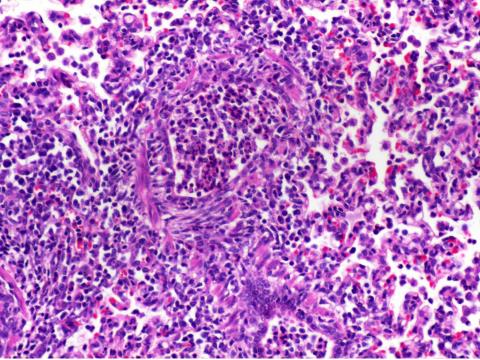

肝小葉内に細胞浸潤を伴う中心性脂肪変性が認められた。(病理スライド1)